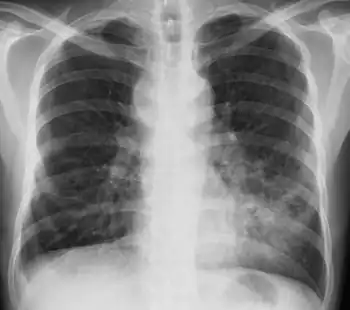

Mycobacterium avium complex infection-increased haziness at left lower lung field with obliteration of cardiac border

Diagnosis can be achieved through blood cultures or cultures of other bodily fluids such as sputum. Bone marrow culture can often yield an earlier diagnosis but is usually avoided as an initial diagnostic step because of its invasiveness. Many people will have anemia and neutropenia if the bone marrow is involved. MAC bacteria should always be considered in a person with HIV infection presenting with diarrhea.